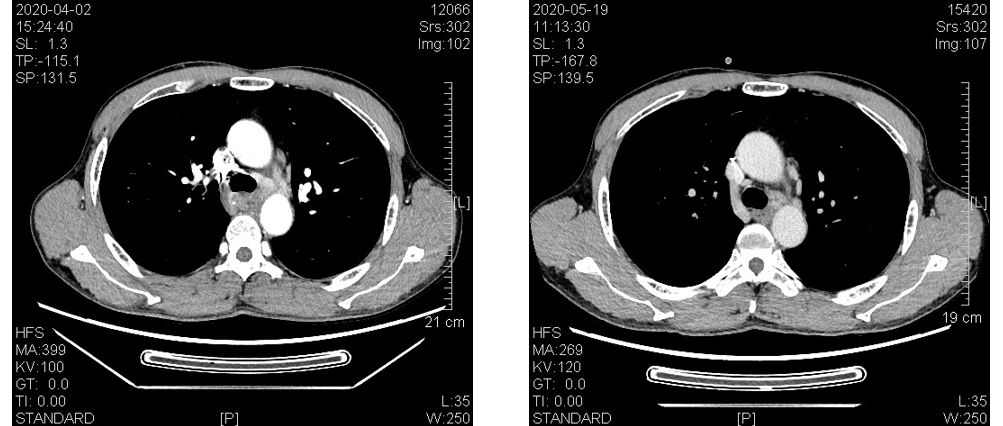

免疫治疗药物在食管癌二线甚至一线治疗中已经取得了令人振奋的临床疗效,人们也期待着其在新辅助治疗方面能够同样带来惊喜!本期我们将分享一例IVA期食管癌通过术前新辅助...

免疫治疗药物在食管癌二线甚至一线治疗中已经取得了令人振奋的临床疗效,人们也期待着其在新辅助治疗方面能够同样带来惊喜!本期我们将分享一例IVA期食管癌通过术前新辅助...